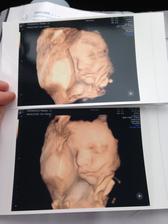

Tehu 2016 (naše druhé bábätko)

Krásne tehuľkovanie 💗💗